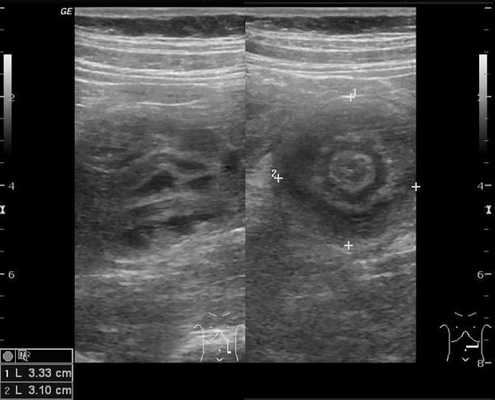

На рисунках 2 и 3 отображена ультразвуковая картина кишечной инвагинации.

Рис. 3. Симптом «псевдопочки»

Комментарии: основным методом в дополнительной диагностике инвагинации кишечника является УЗИ органов брюшной полости. Этот метод обладает 100-процентной диагностической достоверностью и специфичностью в отношении инвагинации кишечника. УЗ-признаками инвагинации кишечника является обнаружение симптома «мишени» или «псевдопочки». Симптом «мишени» заключается в наличии на поперечном срезе двух колец низкой эхоплотности, разделенных гиперэхогенным кольцом. Симптом «псевдопочки» виден на продольном срезе и представляет собой наслаивающиеся друг на друга гипер- и гипоэхогенные слои.